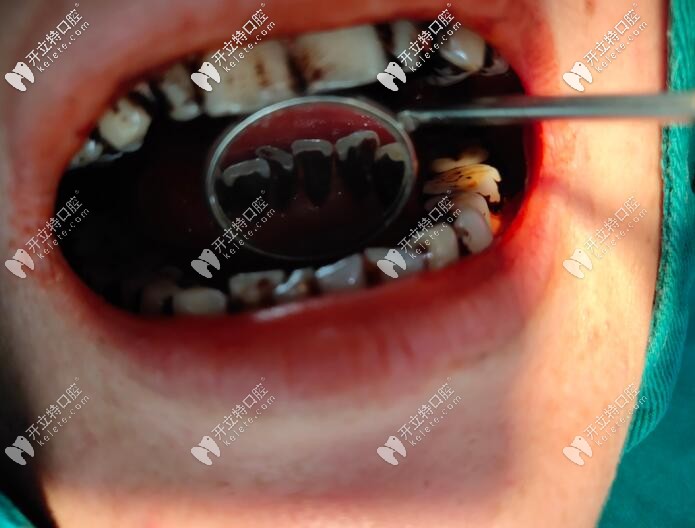

潔牙前牙齒

上面這位顧客煙漬牙比較厲害 ,一張口真臟兮兮的感覺,不僅影響形象,重要的是危害身體健康。

煙漬牙洗牙前

潔牙前牙齒背面